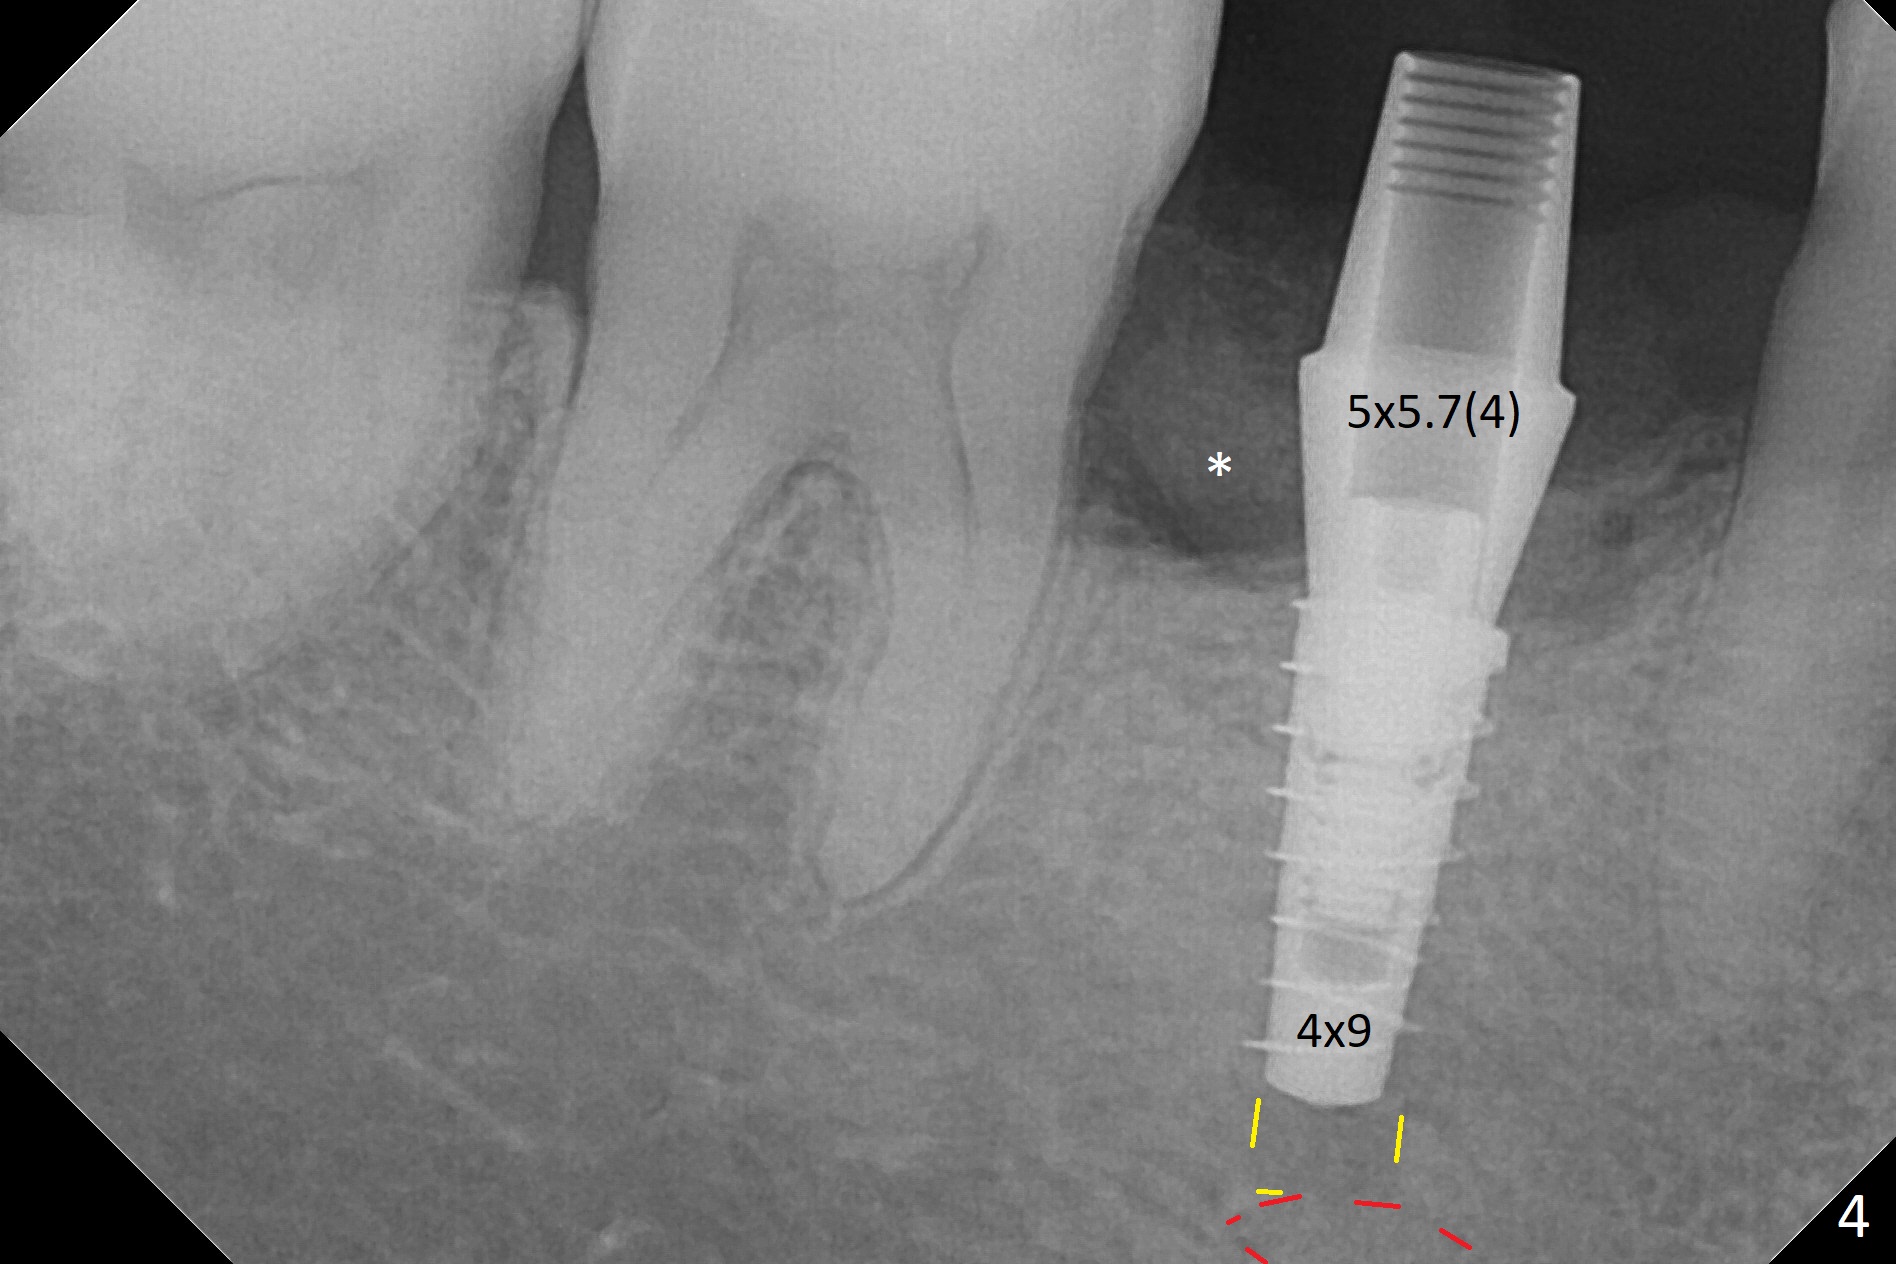

The retained deciduous tooth (lower right 2nd molar, Fig.1 T) has buccal apical infection and recession. After extraction, the initial depth of osteotomy is 11 mm over the flat socket bottom (Fig.2) without visible Mental Loop. Following 3.8 mm Magic Drill for 11 mm, a 4x11 mm dummy implant is placed partially due to hard bone; it appears that the apical osteotomy (Fig.3 yellow outline) overlaps the Mental Loop (red dashed line). For safety, a 4x9 mm IBS implant is placed with insertion torque 40 Ncm; a 5x5.7(4) mm abutment is immediately placed for an immediate provisional to cover the large socket and keep Vera graft in place (Fig.4 *). There is no postop paresthesia, probably due to the fact that the osteotomy is lingual to the Mental Loop. The provisional remains in place 7 days postop; its margin (Fig.5 arrow) covers the socket. The margin of the provisional is trimmed 1 month postop. Impression is taken nearly 3 months postop (Fig.6). The buccal plate looks atrophic 3 months postop (Fig.7 (immediately before cementation)), although there is no sign of periimplantitis. In the future, insert the immediate provisional inside of the buccal gingiva to make the buccal gingiva look bulky instead of buccal to it (Fig.5). The second drawback of placing an implant at the deciduous tooth area is that the crown is wide mesiodistally if orthodontic treatment is not rendered. Although there is lower anterior crowding, the patient declines orthodontic treatment. The bone density around the implant increases 7 months post cementation (Fig.8 *). The higher density bone seems to extend coronally 1 year 7 months post cementation (Fig.9). The dense bone apparently extends toward the abutment as well 3 years 5 months post cementation (Fig.10 curved arrows).